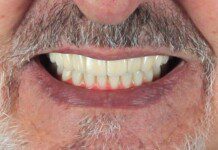

At 4 months, the spacing is ideal. The day the orthodontic brackets are removed, the teeth are prepared for 5 veneers and 1 crown. This decision was based on the amount of tooth structure loss on the right central incisor.

The key to preventing tooth movement is to make the temporaries this day. The temporary restorations will hold the teeth from moving. Please excuse the cement at the right front tooth, this picture was taken before cement removal.